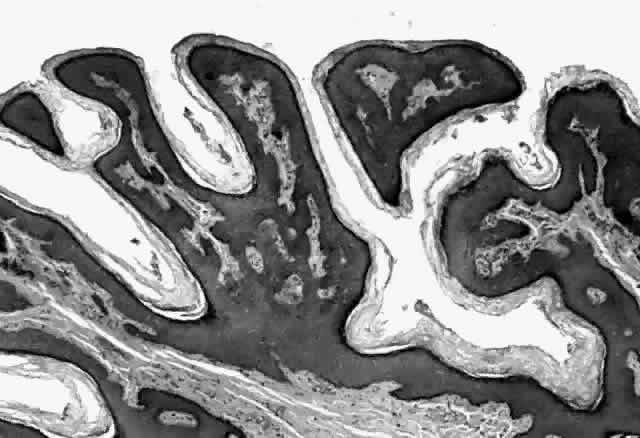

Molluscum contagiosum is a papule with lobular downgrowth of epithelium into the dermis and a central “crater” on the surface (Fig. 11). The epithelium and infected cells demonstrate hyperplasia. Basal cells divide more rapidly (6.1 day turnover decreasing to 3.4 days) and infected cells show more rapid migration through the epithelium as well as cessation of host DNA transcription.121,122 Each lobule demonstrates a progression from base to top. The malpighian cells contain eosinophilic elementary bodies (Fig. 12). These coalesce to form a hyaline molluscum body (HendersonPaterson body).123 The cytoplasmic molluscum bodies increase in size until they distort and displace the nucleus, sometimes becoming larger than the original host cell (Fig. 13). At the top of the lobule in the granular cell layer, the Henderson-Paterson inclusion body changes from eosinophilic to basophilic. When the overlying stratum corneum loses its integrity, the crater is formed (see Fig. 10). Microdissection revealed124 and scanning electron microscopy confirmed125 the presence of a sac surrounding the viral inclusion body within each cell, which has been speculated to provide an immunologically sheltered site for viral reproduction.

Fig. 11. Molluscum contagiosum, histology. Low-power view of lobular epithelial downgrowth and central umbilicated crater. (Original magnification × 50)

Fig. 12. Molluscum contagiosum, histology. Evolution of molluscum bodies from base (left) to center of lobule (right). (Original magnification × 200)

Fig. 13. Molluscum contagiosum, histology. High-power view of transition zone. Molluscum bodies are apparent (right). Note the dark, displaced nuclei. (Original magnification × 400)